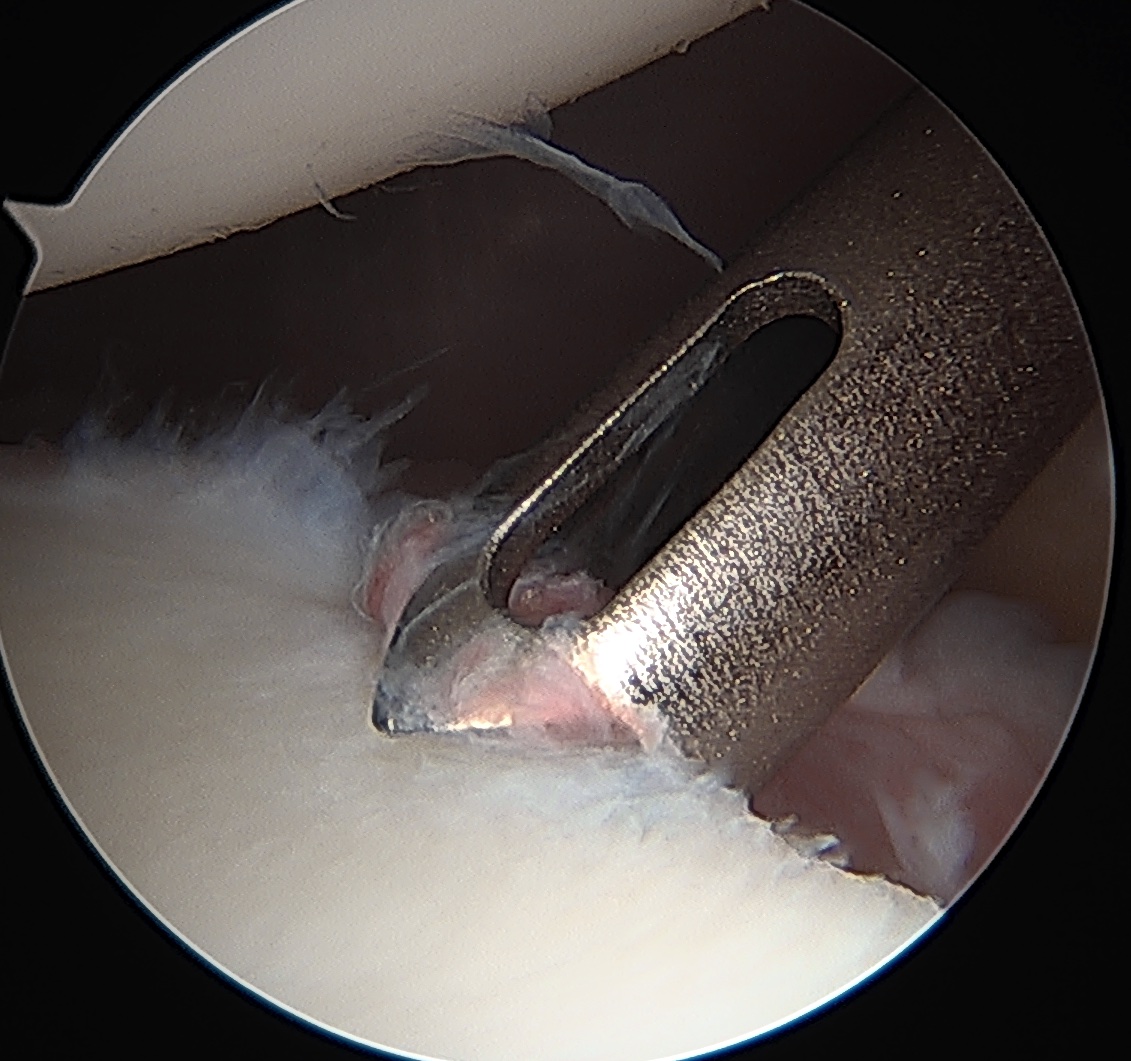

Posterior labral repair

Posterior capsular plication

Arthroscopic posterior labral repair / capsular plication

Technique

- curved anchors very useful